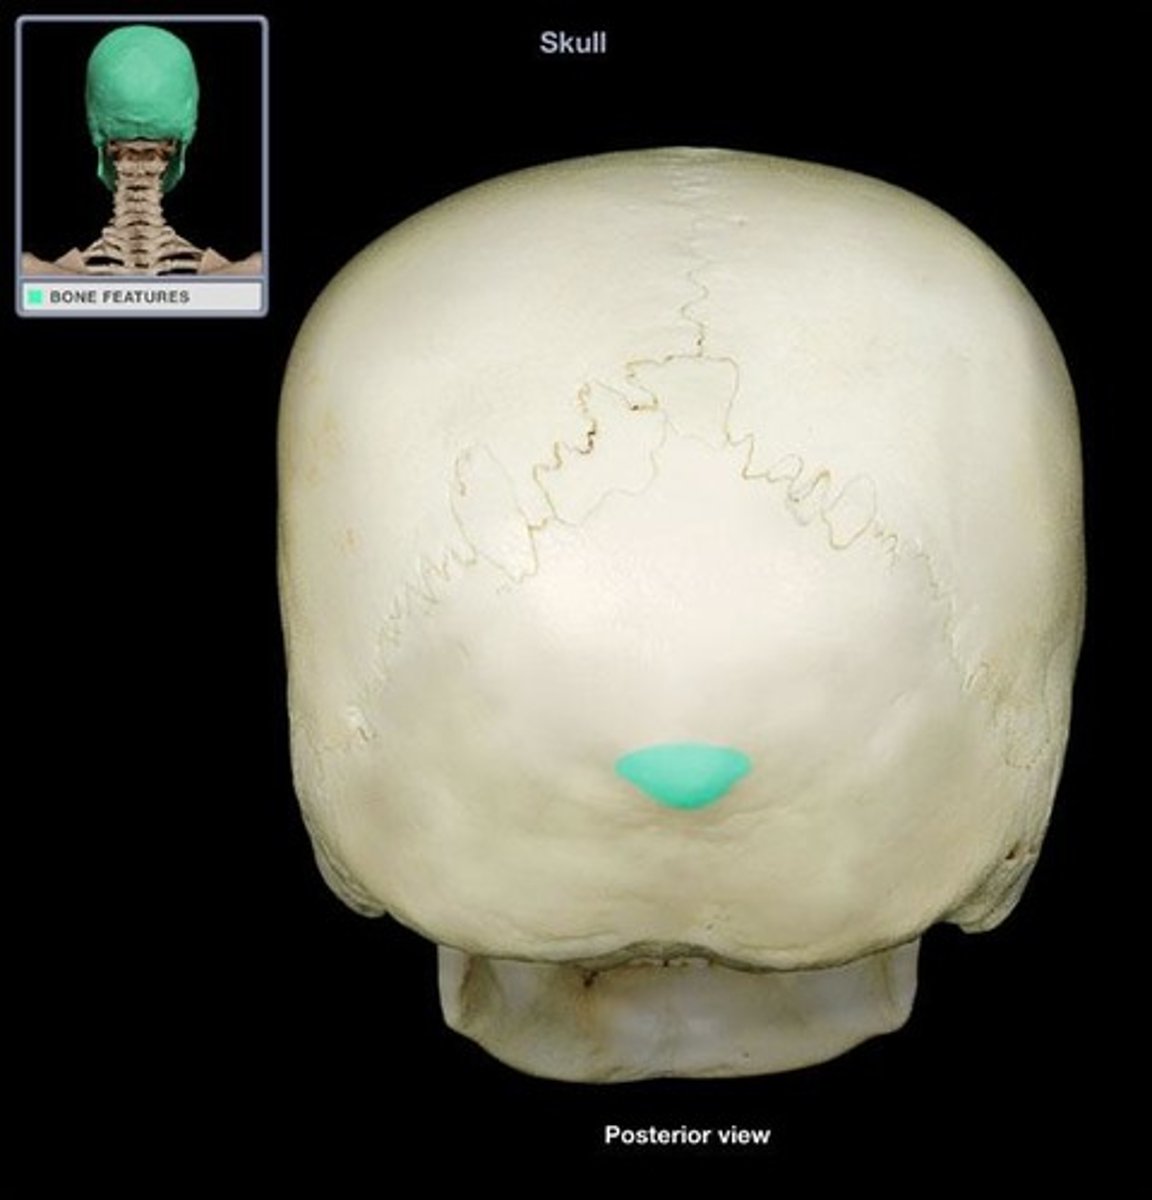

external occipital protuberance

bump on back of head where the trapezius and ligmentum nuchae attach